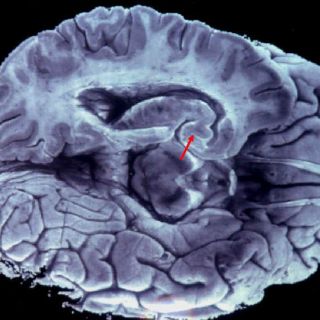

El banco de cerebros está ubicado en Ciudad de México, en el departamento de Fisiología, Biofísica y Neurociencias del Cinvestav, y ahí se guardan cerebros seccionados en mitades, una parte de las cuales se mantiene en ultracongeladores a 90 grados bajo cero, y las otras sumergidas en paraformaldehído -una solución química- a cuatro grados.

El resto se somete a estudios de inmunohistoquímica, en los que se analizan las lesiones características que el Alzheimer produce en el cerebro, como las placas neuríticas y el aumento de marañas neurofibrilares.